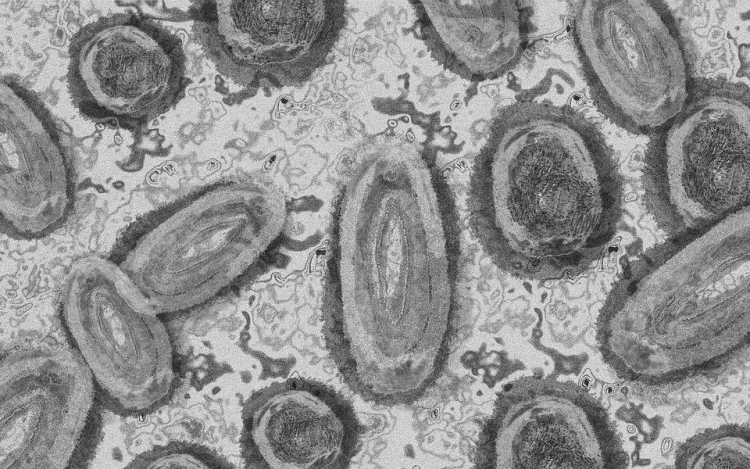

Meghaladta a 13 ezret a majomhimlő-fertőzöttek száma az Egyesült Államokban, a legtöbb esetet Kaliforniában és New York államban regisztrálták.

Az amerikai járványügyi és betegségmegelőzési központ (CDC) szerdán közölt friss tanulmánya szerint a járvány ugyan elsősorban szexuális érintkezés útján terjed, de a fertőzöttek egy része tömegrendezvényeken kapta meg a vírust. A hivatal arra hívja fel a figyelmet, hogy a majomhimlővel bárki megfertőződhet, ha másokkal közeli testi kapcsolatba kerül, akár bőrfelületek érintkezése révén.

A legutóbbi adatok szerint 13 500 fölött van az igazolt fertőzöttek száma, az esetek csaknem felét Kalifornia, New York és Florida államokban regisztrálták.